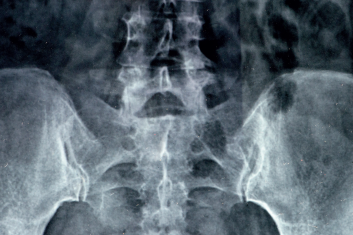

Terapia stawu krzyżowo-biodrowego

Testy i techniki terapii manualnej opisane w tym artykule są bardzo przydatne w celu zidentyfikowania problemu, ustalenia planu terapeutycznego i...